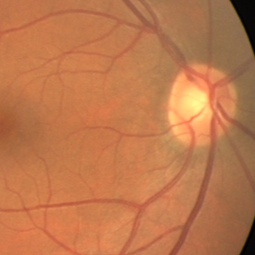

Semantic segmentation of blood vessels is an important task in medical image analysis, but its progress is often hindered by the scarcity of large annotated datasets and the poor generalization of models across different imaging modalities. A key aspect is the tendency of Convolutional Neural Networks (CNNs) to learn texture-based features, which limits their performance when applied to new domains with different visual characteristics. We hypothesize that leveraging geometric priors of vessel shapes, such as their tubular and branching nature, can lead to more robust and data-efficient models. To investigate this, we introduce VessShape, a methodology for generating large-scale 2D synthetic datasets designed to instill a shape bias in segmentation models. VessShape images contain procedurally generated tubular geometries combined with a wide variety of foreground and background textures, encouraging models to learn shape cues rather than textures. We demonstrate that a model pre-trained on VessShape images achieves strong few-shot segmentation performance on two real-world datasets from different domains, requiring only four to ten samples for fine-tuning. Furthermore, the model exhibits notable zero-shot capabilities, effectively segmenting vessels in unseen domains without any target-specific training. Our results indicate that pre-training with a strong shape bias can be an effective strategy to overcome data scarcity and improve model generalization in blood vessel segmentation.